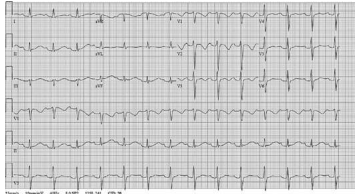

Um paciente com dor crônica compareceu ao ambulatório

de clínica médica. Ele fazia uso crônico de metadona oral

e descreveu a sua dor atualmente como suportável. O

homem apresentou o resultado de ECG a seguir.

Com base nesse caso clínico hipotético, assinale a opção que apresenta a conduta adequada.

Com base nesse caso clínico hipotético, assinale a opção que apresenta a conduta adequada.